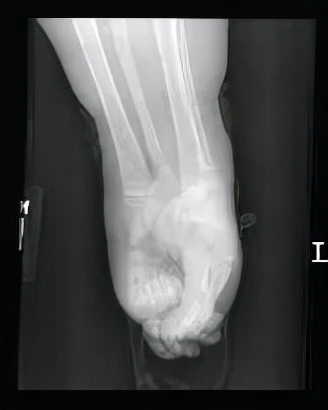

从大腿内侧开始,女孩希洛的下肢便已经出现粘连,一直延续到了脚底。

畸形的粘连将婴儿的下肢完全裹在了一起,连同无法分开的双侧脚趾,缠绕成了童话中美人鱼的模样。

但让人感到遗憾的是,由于女孩希洛的下肢血管分布不规律,且肾脏位置特殊,医生们无法为她施行手术,否则她将会有生命危险。